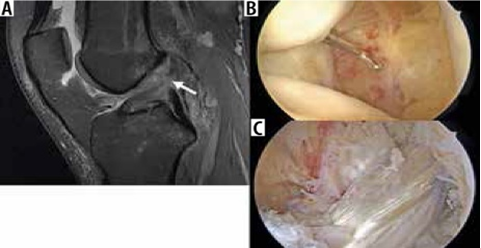

Hình 3. Hình ảnh cộng hưởng từ có trọng số mật độ proton sagital có sụn chêm bên dạng đĩa với tín hiệu tăng trong sụn.

Chẩn đoán rách sụn chêm bao gồm tín hiệu tuyến tính trong sụn tiếp xúc với bề mặt khớp trên hoặc dưới của sụn chêm hoặc một khiếm khuyết trong hình dạng bình thường của sụn chêm [4].